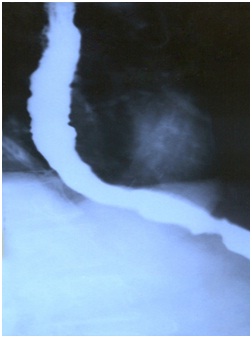

Endoscopy revealed changes of 'Beak-like narrowing' of the lower end of the esophagus and reduction in the motility of the Esophagus, which is diagnostic of Achalasia Cardia. The stomach and duodenum were normal.

Before the treatment

Beak-like narrowing oesophageus because of stricture